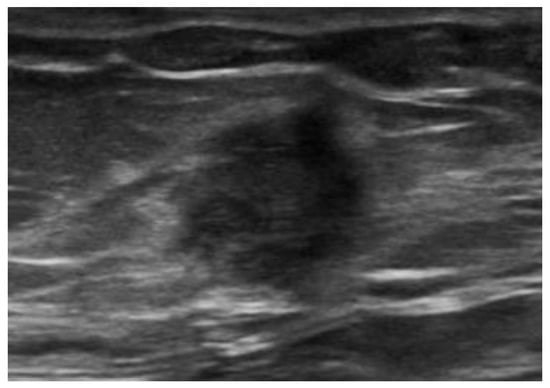

Figure 17. Endometrioma of the abdominal wall on US: heterogeneously hypoechoic, round, or oval-shaped nodule, with scattered internal echoes.

US demonstrates heterogeneously hypoechoic, round or oval-shaped nodules or masses, with scattered internal echoes, and small cystic areas [9,50,53,54], surrounded by a hyperechoic rim [55] (Figure 17).